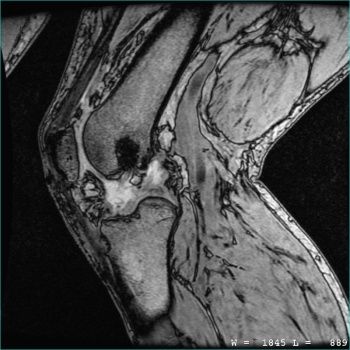

- Musculoskeletal (MSK) Imaging

Combines the high fidelity Head & Torso scan with a detailed spine evaluation to detect disc herniation, spinal cord abnormalities, and spinal degeneration. Also scans for musculoskeletal conditions, fatty liver disease, and multiple sclerosis. Ankles may not be visible for people taller than 5’9″ or 175cm.